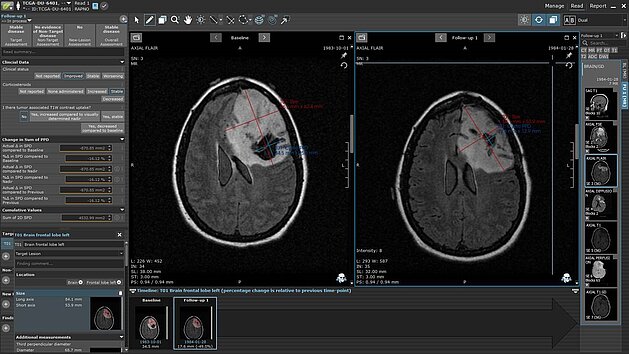

More automation within mint Lesion™? Automated context-dependent template selection, filtering of relevant questions or even fully automated organ and…

Emily Ferris and Alex Arbuckle describe how using mint Lesion™ has enhanced their clinical trial operations, enabling “a more cooperative approach…